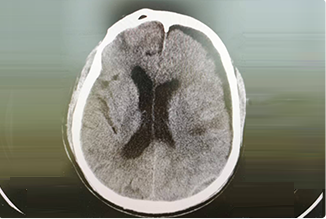

从事神经外科工作30年,擅长脑与脊髓血管类疾病、肿瘤、外伤等疾病的诊断与治疗,尤其擅长神经介入治疗各类脑血管疾病。累计完成介入栓塞颅内动脉瘤2000多例,颅内血管畸形数百例,夹闭颅内动脉瘤数百例,手术颅内与脊髓肿瘤数百例。在脑和脊髓血管病、肿瘤、外伤等方面有丰富的经验和较深造诣。

精通颅内动脉瘤介入栓塞和手术夹闭双技术,系统掌握脑动静脉畸形、颈内动脉海绵窦漏、硬脑膜动静脉漏等颅内血管疾病的诊疗和手术,精通颈动脉、椎动脉狭窄的血管内重建技术,以及颈动脉狭窄的内膜剥脱手术技术。在颅内肿瘤、椎管内肿瘤、颅脑损伤、高血压脑出血等疾病的诊治和手术,脑功能性疾病立体定向手术治疗等方面也积累了丰富的经验。

擅长脑血管病(出血与缺血)的神经介入与微创手术,能熟练开展脑外伤、重度颅脑损伤的救治工作。